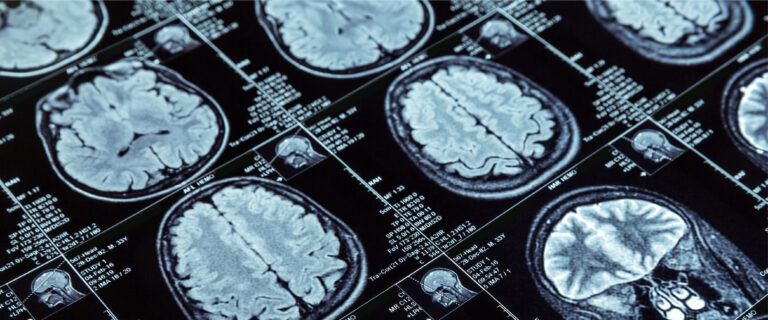

Artificial Intelligence may diagnose dementia in a day

This article was taken from: https://www.bbc.co.uk/news/health-57934589     By Pallab Ghosh Science correspondent     Scientists are testing an artificial-intelligence system thought to be capable of diagnosing dementia after a single brain scan.     It may also be able to predict whether the condition will remain stable for many years, slowly deteriorate or need…